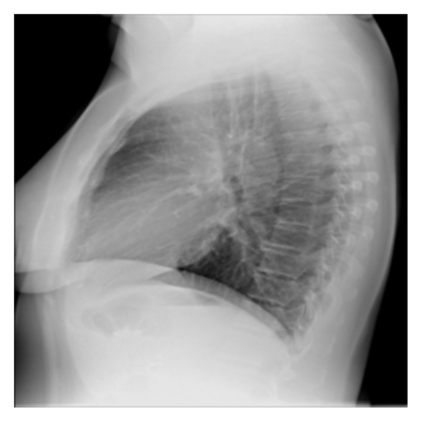

The evaluation of infectious disease processes on radiologic images is an important and challenging task in medical image analysis. Pulmonary infections can often be best imaged and evaluated through computed tomography (CT) scans, which are often not available in low-resource environments and difficult to obtain for critically ill patients. On the other hand, X-ray, a different type of imaging procedure, is inexpensive, often available at the bedside and more widely available, but offers a simpler, two dimensional image. We show that by relying on a model that learns to generate CT images from X-rays synthetically, we can improve the automatic disease classification accuracy and provide clinicians with a different look at the pulmonary disease process. Specifically, we investigate Tuberculosis (TB), a deadly bacterial infectious disease that predominantly affects the lungs, but also other organ systems. We show that relying on synthetically generated CT improves TB identification by 7.50% and distinguishes TB properties up to 12.16% better than the X-ray baseline.